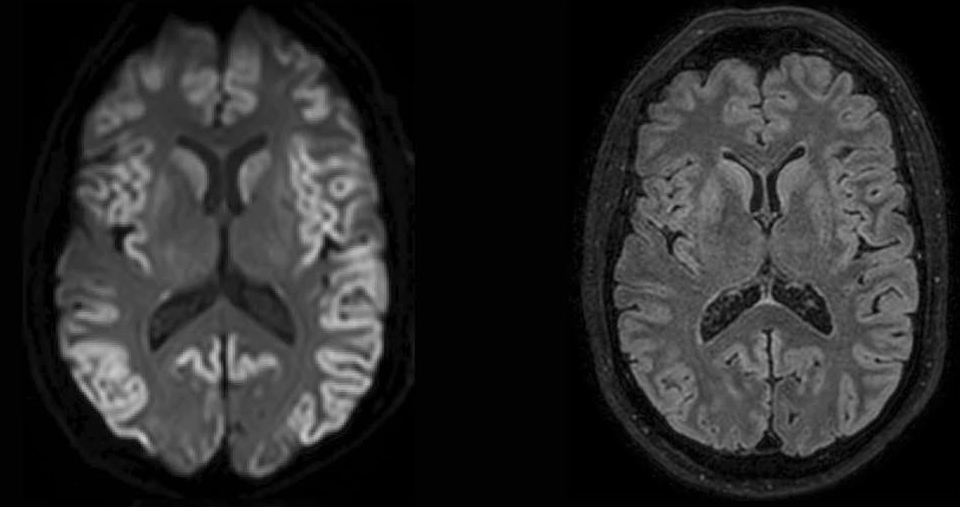

Comatose patients after cardiac arrest have an uncertain prognosis. In about half of all, hypoxic brain damage precludes recovery of consciousness. Early predictors of functional recovery can prevent futile continuation of intensive care treatment. With the current recommended predictors, including neurological examination, EEG, SSEP, and NSE blood levels, a reliable prognosis is possible in about half of all patients. New, complementary predictors are needed.

The Cracking Coma study is a longitudinal multicenter cohort study to establish the additional predictive value of various MRI techniques and derive multimodal prediction models to optimize outcome prediction. Candidate MRI factors include diffusion (DWI, DTI) and resting state functional MRI measures. The study protocol can be found here.